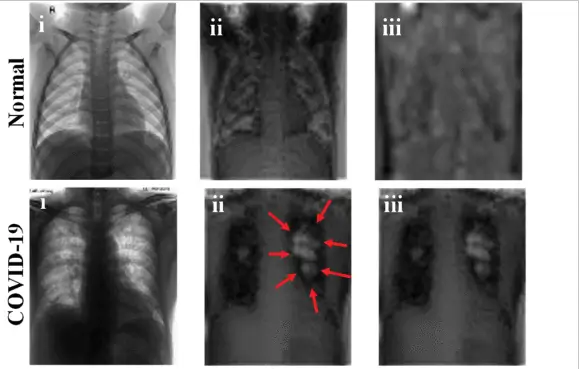

COVID Radiology Images

chest X-ray images in PNG format that are divided into two categories - COVID positive and normal.